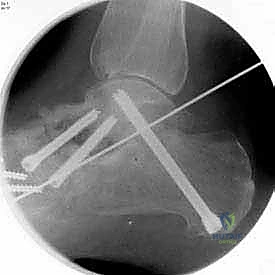

بعد التأكد من الوضعية المثالية للعظام، يتم تثبيتها بقوة باستخدام مسامير معدنية مجوفة من التيتانيوم (Cannulated Screws) أو شرائح معدنية خاصة. يتم إدخال المسامير تحت توجيه الأشعة السينية المباشرة (Fluoroscopy) داخل غرفة العمليات لضمان الدقة المتناهية. هذه المسامير تضغط العظام معاً وتمنع أي حركة حتى يحدث الالتئام التام.